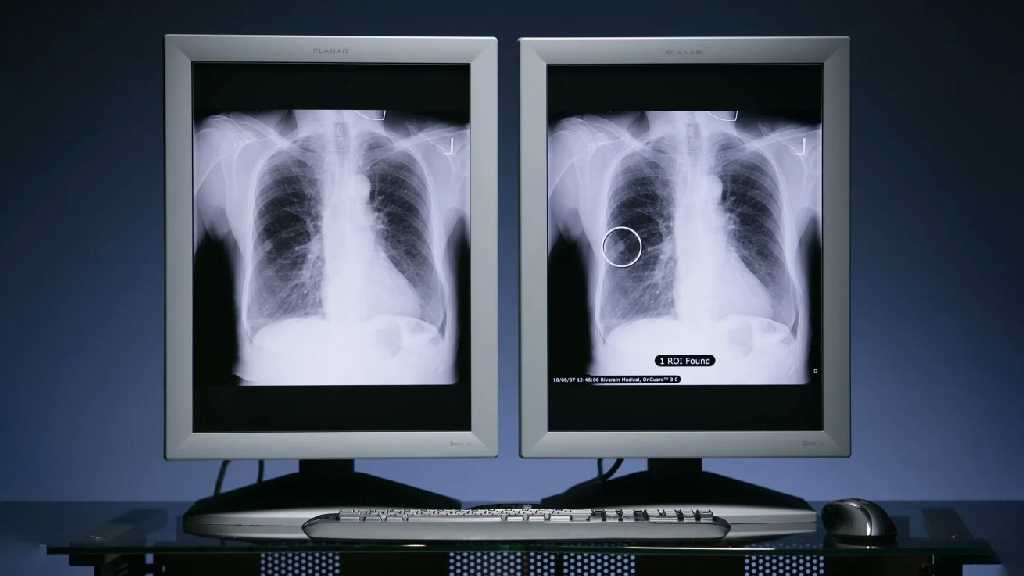

চীনা ও মার্কিন বিজ্ঞানীদের নেতৃত্বে একধরনের জটিল ফুসফুস ক্যানসারের চিকিৎসায় নতুন একটি ওষুধের আন্তর্জাতিক ক্লিনিক্যাল ট্রায়াল চলছে। এই ট্রায়ালে ইতিমধ্যে প্রমাণ পাওয়া গেছে, মুখে খাওয়ার ওই ওষুধ আগের চিকিৎসার তুলনায় বেশি নিরাপদ ও কার্যকর।বিস্তারিত

চীনা ও মার্কিন বিজ্ঞানীদের নেতৃত্বে একধরনের জটিল ফুসফুস ক্যানসারের চিকিৎসায় নতুন একটি ওষুধের আন্তর্জাতিক ক্লিনিক্যাল ট্রায়াল চলছে। এই ট্রায়ালে ইতিমধ্যে প্রমাণ পাওয়া গেছে, মুখে খাওয়ার ওই ওষুধ আগের চিকিৎসার তুলনায় বেশি নিরাপদ ও কার্যকর।বিস্তারিত

চীনা ও মার্কিন বিজ্ঞানীদের নেতৃত্বে একধরনের জটিল ফুসফুস ক্যানসারের চিকিৎসায় নতুন একটি ওষুধের আন্তর্জাতিক ক্লিনিক্যাল ট্রায়াল চলছে। এই ট্রায়ালে ইতিমধ্যে প্রমাণ পাওয়া গেছে, মুখে খাওয়ার ওই ওষুধ আগের চিকিৎসার তুলনায় বেশি নিরাপদ ও কার্যকর।বিস্তারিত

চীনা ও মার্কিন বিজ্ঞানীদের নেতৃত্বে একধরনের জটিল ফুসফুস ক্যানসারের চিকিৎসায় নতুন একটি ওষুধের আন্তর্জাতিক ক্লিনিক্যাল ট্রায়াল চলছে। এই ট্রায়ালে ইতিমধ্যে প্রমাণ পাওয়া গেছে, মুখে খাওয়ার ওই ওষুধ আগের চিকিৎসার তুলনায় বেশি নিরাপদ ও কার্যকর।বিস্তারিত